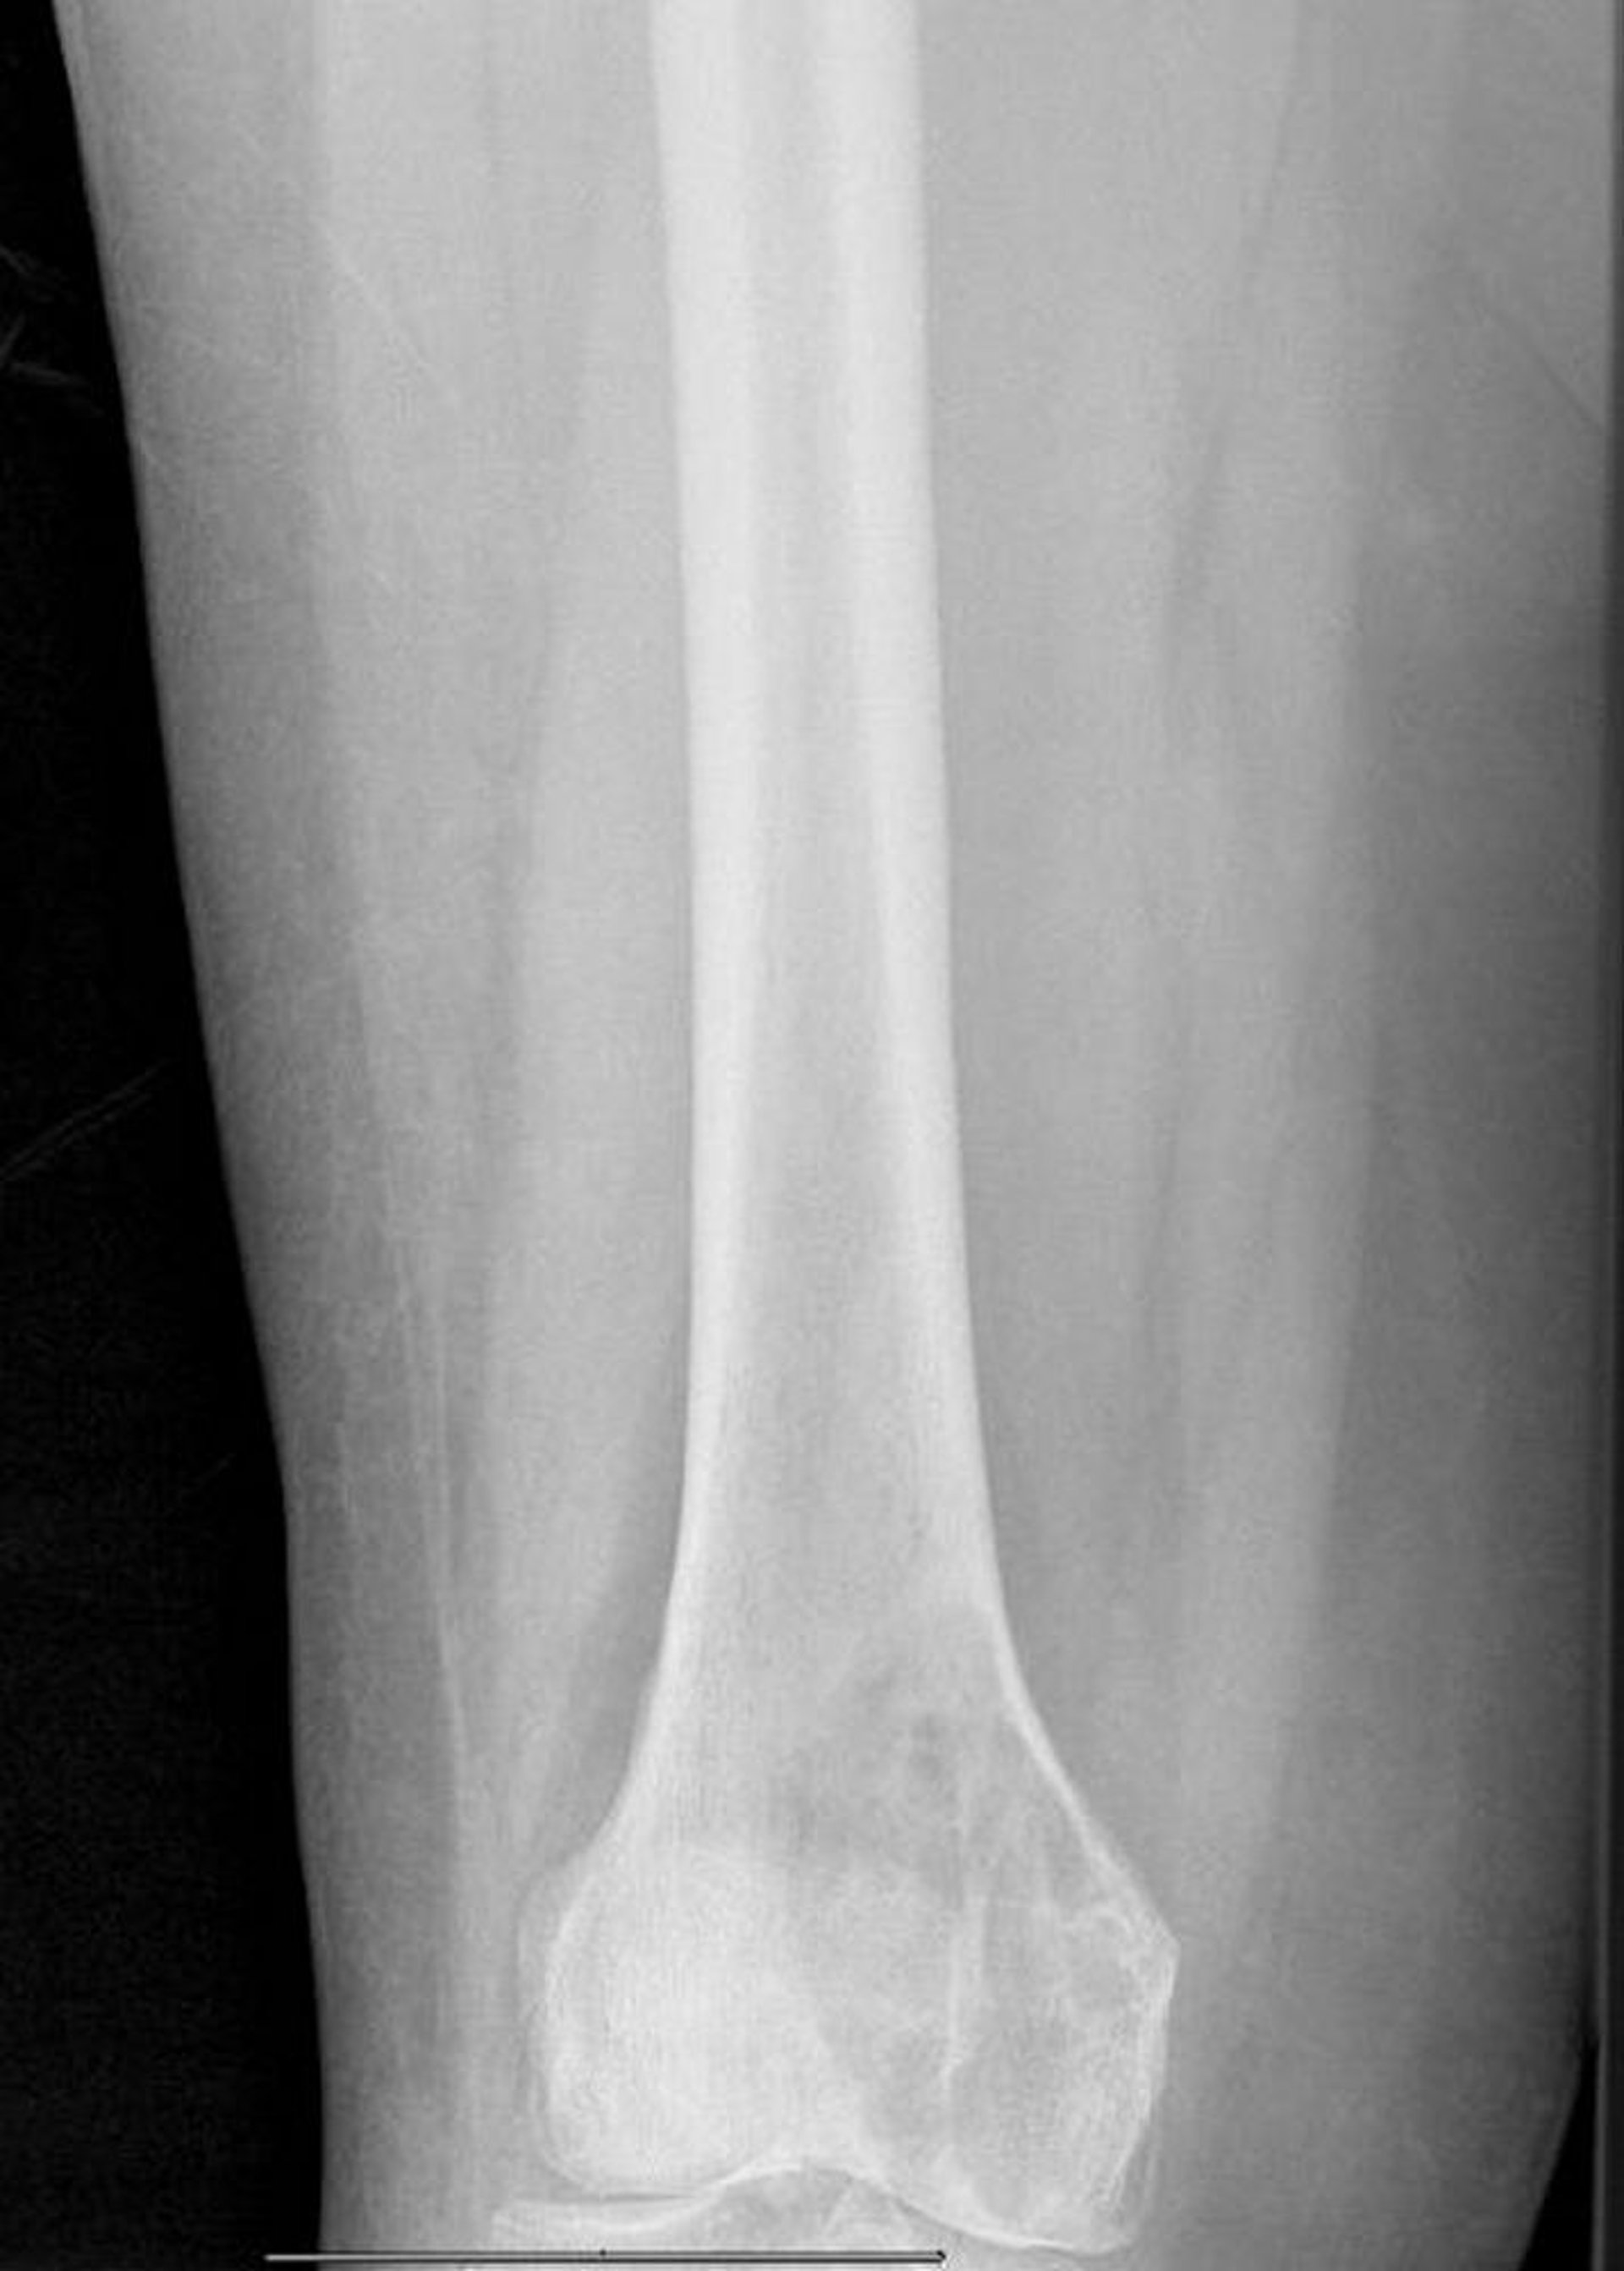

Metástase lítica no fêmur distal

Essa radiografia mostra uma grande lesão lítica metastática do côndilo medial femoral com fratura patológica iminente.

Imagem cedida por cortesia de Michael J. Joyce, MD, and David M. Joyce, MD.